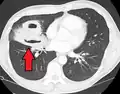

Lung abscesses are often on one side and single involving posterior segments of the upper lobes and the apical segments of the lower lobes as these areas are gravity dependent when lying down. Presence of air-fluid levels implies rupture into the bronchial tree or rarely growth of gas forming organism.

Pulmonary abscess on CT scan -

Pulmonary abscess on CXR -